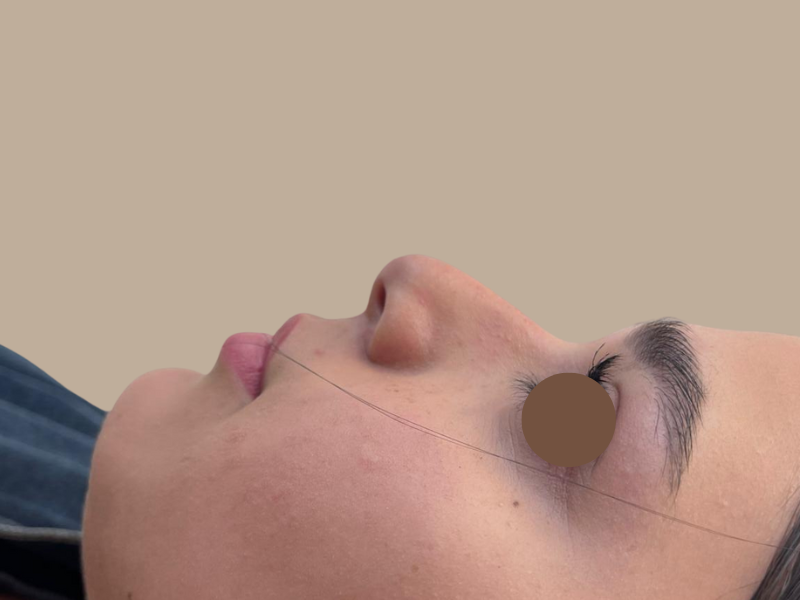

לפני ואחרי

לפניכם דוגמה למטופלות רשת מרפאות פרופורציה:

עבור מטופלים אשר עברו ניתוח אף ומרגישים כי התוצאה עדיין אינה מיטבית, הליך פיסול האף מאפשר ביצוע של מקצה שיפורים נקודתי למילוי וטיפול באסימטריה. ניתן לגשת לייעוץ אצל רופא אסתטיקה בעל ניסיון בתחום בנוגע לפיסול אף בתום שנה מהניתוח, לאחר החלמה מלאה וההתייצבות תצורת האף.